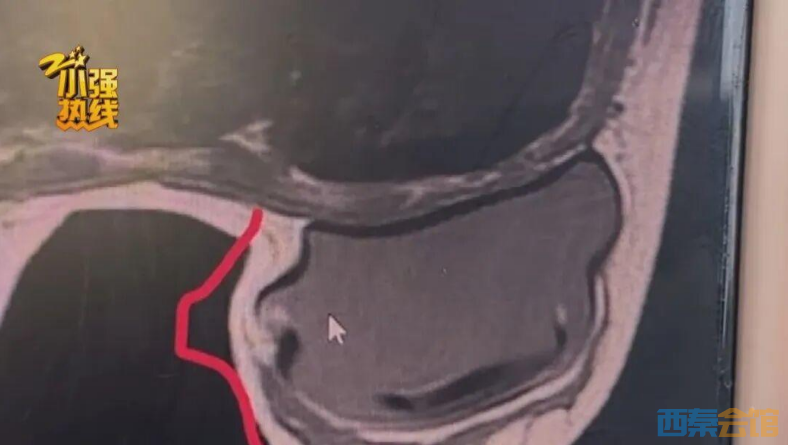

杭州的王女士向《小强热线》求助,她在去年4月经人推荐,在“杭州妍尚医疗美容门诊部"花费3.4万多元做了隆胸手术,但术后出现了左右不对称的情况,更让她糟心的是,当时的中间人还把她拉黑了,而原先做手术的医院,也被转让了。

去年4月,杭州的王女士经微信名为“晓晓”的美容顾问推荐,在“杭州妍尚医疗美容门诊部”花费3.4万多元做了隆胸手术。术后她一直感觉不适,且双侧乳房出现明显的不对称。